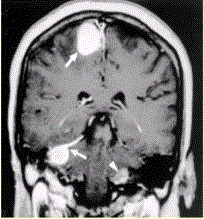

问题 患者男,20岁,头痛、步态不稳。MRI显示如下图。 下图影像学表现可诊断为

选项 A.神经纤维瘤病Ⅱ型 B.神经纤维瘤病Ⅰ型 C.多发脑膜瘤 D.多发神经鞘瘤 E.多发脑转移瘤

答案 A